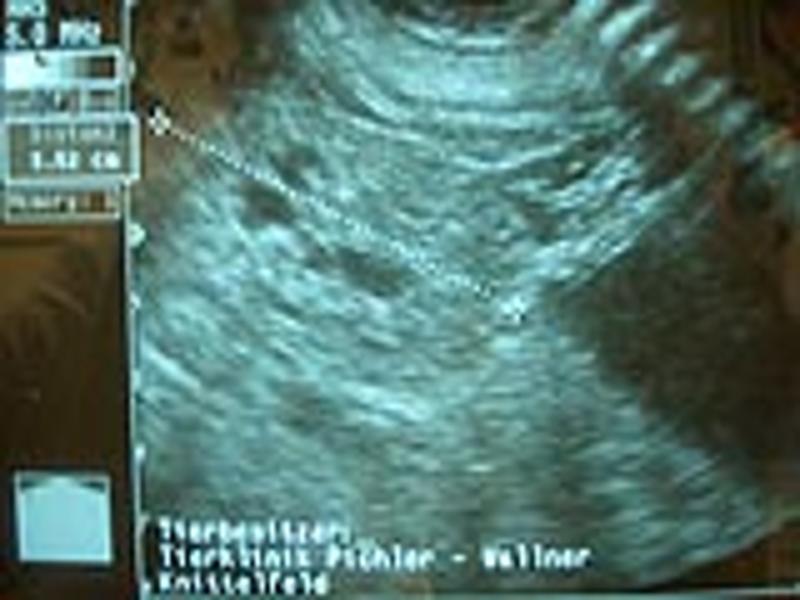

Ultraschall

Die Möglichkeit einer Ultraschalluntersuchung ist wie bei Trächtigkeitsuntersuchungen, neoplastischen Umfangsvermehrungen im Abdominalraum oder Veränderungen im Urogenitaltrakt wie zB. Ovarialzysten oder Pyometra sehr hilfreich. Mit unserem mobilen Ultraschallgerät können wir auch Trächtigkeitsuntersuchungen bei Pferden und Rindern, aber auch eine genaue Untersuchung bei Sehnenverletzungen durchführen.